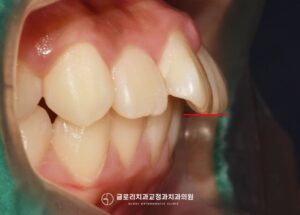

|상봉역 교정치과|앞니 벌어짐과 뻐드러짐, 동시에 해결하는 교정 방법

안녕하세요, 상봉역 교정치과 김정은 원장입니다. ^^ 연말이 다가오면서 송년회나 모임 자리에서 사진을 찍을 일이 부쩍 늘어납니다. 거울 속에 비친 모습이나 누군가 찍어준 사진을 보다 보면 유독 앞니 문제가 눈에 들어올…